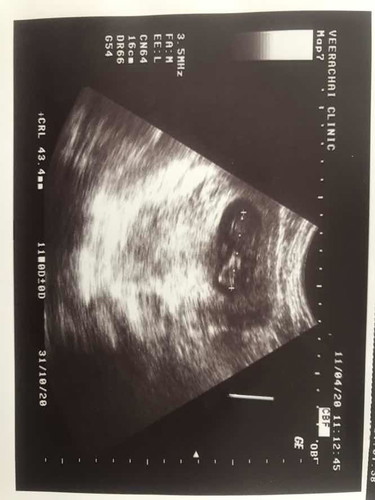

ภาวะแท้งคุกคาม

เราท้องได้สามเดือนแล้ว เคยมีประวัติแท้งลูกคนแรกตอน7 เดือน พอมาท้องรอบนี้เราเผลอไปยกน้ำทำไห้มีเลือดออก หมอฉีดยากันแท้งไห้ครบ3 เข็มแล้วแต่ยังมีเลือดออกอยู่ ครั้งสุดท้ายที่อุลต้าซาว หมอบอกรกบางมากแล้ว แบบนี้เรามีสิทธิ์ท้องต่อไปได้ไหม มีคุณแม่ท่านไหนมีประสบการณ์ด้านนี้บ้าง ตอนนี้เป็นกังวลมาก ถามหมอแล้วหมอบอกได้แค่ระวัง